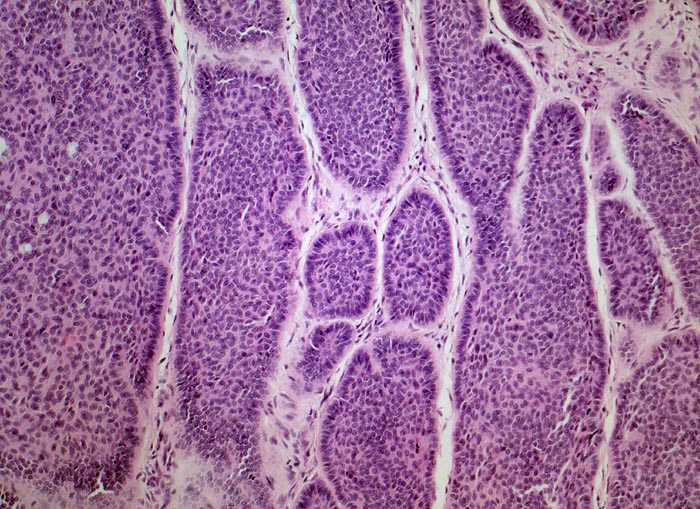

Basaliom

maligner Tumor

Haut, Kopf

Haut

Der Tumor besteht aus soliden Platten aus basaloiden Zellen. Die Zellen am Rand der soliden Zellplatten sind parallel und senkrecht zur Basalmembran ausgerichtet ( Palisadierung). Zwischen den Zellplatten und dem Stroma findet sich stellenweise ein typischer Retraktionsartefakt.

Derber weisser, leicht erhabener Knoten an der Nase.

Histologie

100